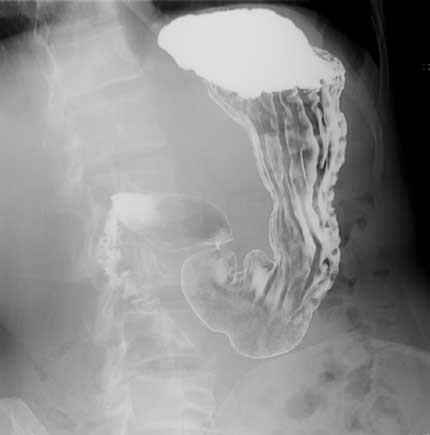

- Un estudio baritado del intestino delgado: es una prueba en la cual se administra un medio de contraste que contiene bario por vía oral y luego se toman radiografías para evaluar el tiempo que tarda el bario en pasar a través del intestino delgado. En pacientes con síndrome de vaciamiento rápido, se puede observar un tránsito acelerado del bario a través del intestino delgado, lo que confirma el diagnóstico.